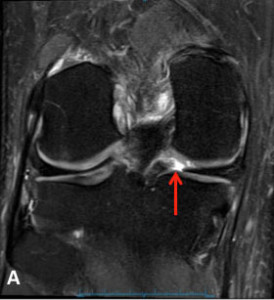

Meniscal Root Tear Meniscal root tears can be seen on coronal, axial and sagittal MRI views. On the sagittal view, as seen in Figure C, there is a “ghost sign” which is indicative of meniscal root tear. A normal, healthy meniscus should look like a dark black triangle; however, as this figure shows the meniscus is much lighter or “ghosted” representing the root tear.